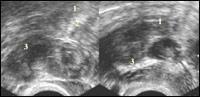

| Рисунок 2

| Эхокартина внематочной беременности Внематочная беременность в интрамурально-истмическом отделе.

| Рисунок 3

| Эхокартина внематочной беременности Обращает внимание выраженное утолщение стенок трубы (1) вокруг плодовместилища.

| Рисунок 4

| Эхокартина внематочной беременности Утолщенный фрагмент трубы с неоднородной внутренней эхоструктурой жидкость в малом тазу

При нарушенной трубной беременности в проекции маточной трубы обнаруживается образование с нечеткими, неровными контурами и гетерогенной, кистозно-солидной структуры, часто в общем конгломерате с яичником.